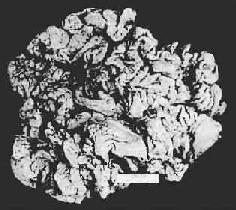

一、胃炎胃炎(gastritis)是胃粘膜的炎性变化,是一种常见病,可分为急性胃炎和慢性胃炎。慢性胃炎可由急性胃炎反复发作迁延而来,但多数因其他全身性因素及胆汁反流至胃内引起。近年发现,从慢性胃炎患者胃粘膜中分离出一种螺旋状弯曲杆菌,命名为弯曲样细菌(campylobacter like organisms,CLO),经研究证明本菌与胃炎之间关系密切,该菌不仅适应胃内高酸环境,还可降解胃粘膜表面被覆粘液使其失去保护作用,故被认为是慢性胃炎的一种病原因素。 (一)急性胃炎 急性胃炎(acute gastritis)常见者有4种: 1.急性卡他性胃炎(acute catarrhal gastritis)多因暴饮暴食引起,亦称刺激性胃炎(irritation gastritis)。胃粘膜充血、水肿有时可见粘膜糜烂。 2.腐蚀性胃炎(corrosive gastritis)由咽下高浓度酸、碱或腐蚀性化学剂引起。病变多较严重,胃粘膜出现坏死、软化溶解。 3.急性蜂窝织炎性胃炎(acute phlegmonous gastritis)少见,是一种弥漫性化脓性炎,病情较重。可由金黄色葡萄球菌、链球菌或大肠杆菌等化脓菌经血行感染(败血症)或直接感染(创伤)侵入胃壁引起。 4.急性出血性胃炎(acute hemorrhagic gastritis)主要表现为胃粘膜急性出血合并轻度坏死。本病发生与服用某些药物(如水杨酸制剂)、过量应用肾上腺皮质激素及过度饮酒有关。 (二)慢性胃炎 慢性胃炎(chronic gastritis)是一种常见病。一般分为表浅性及萎缩性二种。 1.慢性表浅性胃炎(chronic superficial gastritis)本病在胃窦部最为常见,为常见的胃粘膜疾患之一,纤维胃镜检出率高达20%~40%。 【病变】 肉眼观,病变多为多灶性或弥漫性,病变胃粘膜充血、水肿,有时并伴有点状出血或糜烂。镜下,可见炎性病变主要限于粘膜浅层,呈弥漫性或灶状分布。浸润的炎性细胞主要是淋巴细胞和浆细胞,有时可见少量嗜酸性粒细胞及中性粒细胞。此外可见粘膜浅层出现水肿、小出血点或表浅上皮坏死脱落。 2.慢性萎缩性胃炎(chronic atrophic gastritis)本病炎症改变并不明显,主要是胃粘膜的萎缩性变化。此时胃粘膜萎缩变薄,腺体减少或消失。临床上可有胃内游离盐酸减少或缺乏、消化不良,上腹不适或钝痛、贫血等症状。 【病因和分型】 现今将萎缩性胃炎分为A、B二型。已知A型发病与免疫因素关系密切,病人血中可找到抗胃壁细胞微粒体的自身抗体。病变在胃体部,并有维生素B12吸收障碍,常合并恶性贫血,可找到抗内因子抗体。B型的发病则与自身免疫无关,同时并不伴有恶性贫血也找不出自身抗体。其病因可能与吸烟、酗酒或滥用水杨酸类药物(如APC)等有关。B型亦称单纯性萎缩性胃炎,在我国较为多见。其病变部位在胃窦部,有的并可能发生癌变。两型萎缩性胃炎的胃粘膜病变基本一致。 【病变】 胃粘膜薄而平滑,皱襞变浅,有的几乎消失。粘膜表面呈细颗粒状。胃镜检查,可有3个特点:①正常胃粘膜的橘红色色泽消失,代之以灰色;②萎缩的胃粘膜明显变薄,与周围的正常胃粘膜界限明显;③萎缩处因粘膜变薄,粘膜下血管分支清晰可见。 镜下,病变区腺上皮萎缩,腺体变小并可有囊性扩张,常出现上皮化生(假幽门腺化生及肠上皮化生)。在粘膜固有层有不同程度的淋巴细胞和浆细胞浸润。在胃体和胃底部病变区,主要呈现壁细胞消失,其次是主细胞消失和粘液分泌细胞化生。后者称为幽门腺或假幽门腺化生。电镜观察,壁细胞除数量减少外,可见细胞内自噬泡增多,内质网扩张,高尔基器减少,线粒体肿胀,表面微绒毛消失。内质网、高尔基器和微绒毛是壁细胞的功能部分,其减少或消失反映了细胞泌酸功能的低下或消失。在幽门窦病变区,主要改变为幽门腺呈不同程度的萎缩、消失(图10-3)并常有肠上皮化生。胃粘膜表层上皮细胞生长,可形成绒毛样突起,增生的上皮中出现分泌粘液的杯状细胞(图10-4)、具有刷状缘的吸收上皮细胞和Paneth细胞时其形态结构与小肠粘膜相似,故称为肠上皮化生。现知肠上皮化生的胃粘膜易诱发胃癌,多为息肉样腺癌。

图10-4 胃粘膜肠上皮化生 胃粘膜上皮出现多量充满粘液的杯状细胞 3.肥厚性胃炎(hypertrophic gastritis) 又称肥厚性胃病(hypertrophic gastropathy)、Menetrier病。发病原因不明。病变特点是,粘膜肥厚,皱襞加深变宽似脑回状(图10-5)。镜下,腺体肥大增生,腺管延长。粘膜固有层炎性细胞浸润不显著。粘膜表面粘液分泌细胞数量增加,壁细胞及主细胞有时减少。临床上,多数患者有胃酸低下及因蛋白由胃液丧失而致的低蛋白血症。